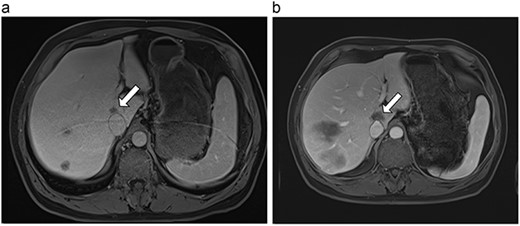

| 2 (4a,b) | 67, M | Colon adenocarcinoma | 8 cycles capecitabine and oxaliplatin | 6 | Laparoscopic microwave ablation | 15 | 35 | 20 | 6 | No |

(a) Pre-ablation MRI demonstrating 15 mm lesion in caudate lobe of liver (image degraded by motion artifact). (b) Post-ablation MRI (20 days postoperatively) demonstrating 35 mm complete ablation of caudate lesion (image degraded by motion artifact).